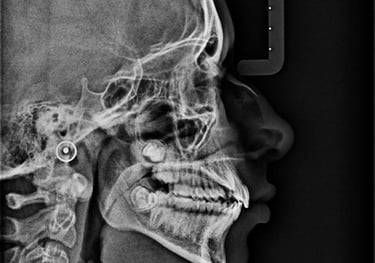

TELERRADIOGRAFIA LATERAL